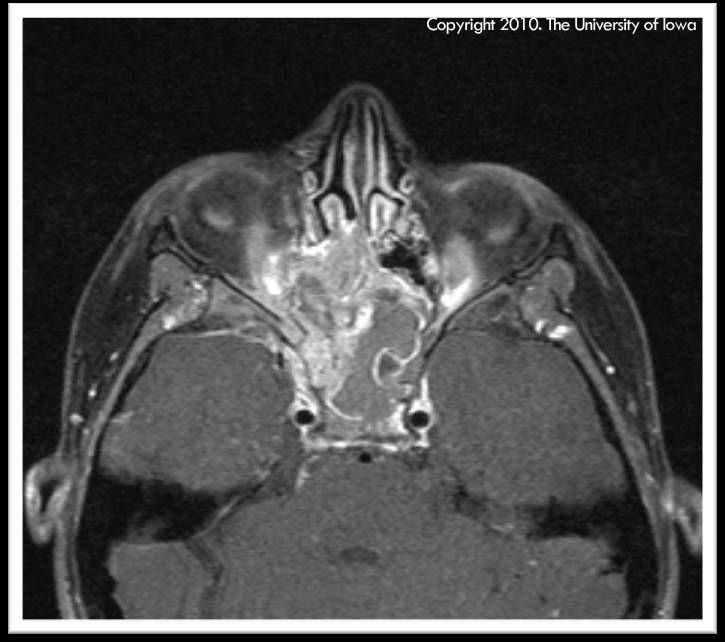

Figure 1, caption below, click on image for higher resolution.

Figure 1: Axial MRI (T1 with fat suppression) showing heterogenous mass originating in the patient's ethmoid and/or sphenoid sinus with intracranial extension and encasement of the right optic nerve causing mass effect on the right medial rectus and right superior oblique muscles (click on image for higher resolution image)

History of Present Illness: The patient is a previously healthy 11-year-old boy who presented to clinic complaining of blurry vision, headaches, and difficulty moving his right eye for the past two weeks. The patient had complained to his mother about these symptoms after his friend had bumped him in the head while they were swimming. The patient's mother brought the patient to their local ophthalmologist to be evaluated. After examining the patient, the ophthalmologist sent the patient to an outside hospital for an MRI of the brain and orbit. The MRI showed a heterogeneous mass originating in the patient's ethmoid and/or sphenoid sinus with intracranial extension and encasement of the right optic nerve causing mass effect on the right medial rectus and the right superior oblique muscles. The patient was subsequently sent to the University of Iowa for further evaluation by the Oculoplastics Service as well as the Pediatric Hematology/Oncology, Otolaryngology, and Neurosurgery Services.